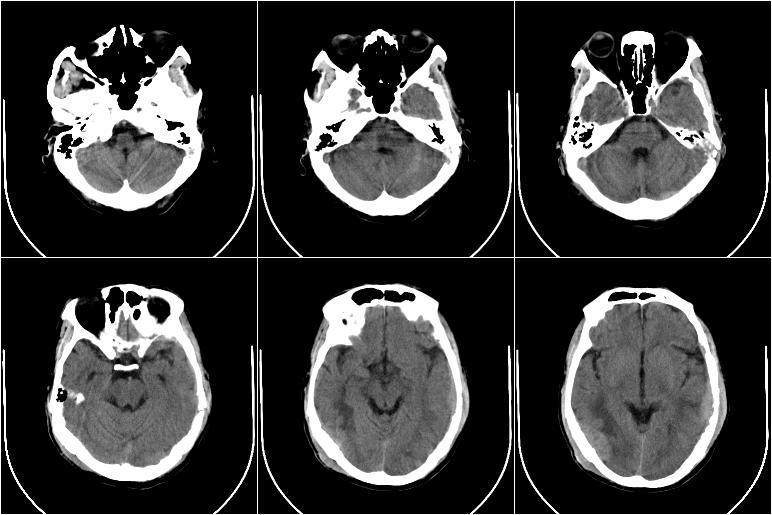

以下是引用边生丽在2009-8-17 11:43:00的发言:[br][br] [br] 右肺中心型癌伴右肺下叶不张、双肺转移并癌性淋巴管炎、心包和双侧胸腔积淮(转移?)、脑转移、肝转移、多骨(颅骨、椎骨)转移。 [br] [br]

以下是引用随光逐影在2009-8-17 14:09:00的发言:[br]支持 右肺中央型癌伴右肺下叶肺不张,纵隔淋巴结转移,双肺转移并癌性淋巴管炎,心包和双侧胸腔积液,脑转移、肝转移、多发性骨(颅骨、脊椎)转移。